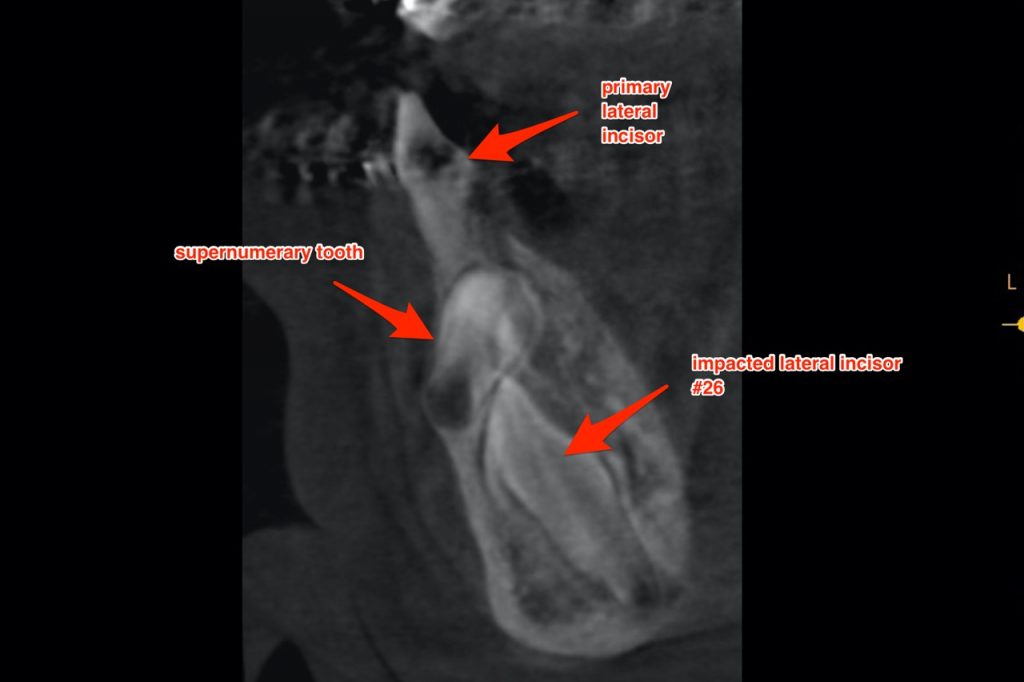

Extraction of Supernumerary Tooth and Exposure of Impacted Lower Lateral Incisor For Orthodontic Eruption

In this video, Dr. H. Ryan Kazemi demonstrates extraction of a supernumerary tooth and exposure technique for orthodontic eruption of impacted tooth #26.addition, he describes the process for immediate placement of a dental implant.